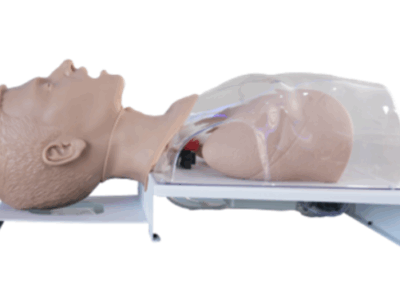

Simuladores de Habilidades Clínicas

Treinamento prático em procedimentos médicos essenciais.